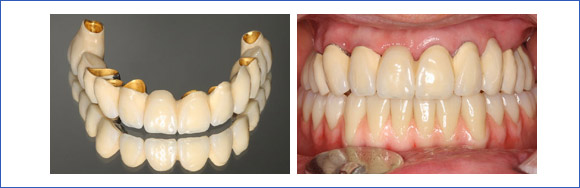

b) Versorgung mit einer großen, festsitzenden Brücke

Versorgung vom zahnlosen Kiefer:

3. Das Eingliedern des Zahnersatzes

Nach 3-5 Monaten Einheilzeit kann der Zahnersatz auf dem Implantat befestigt werden.